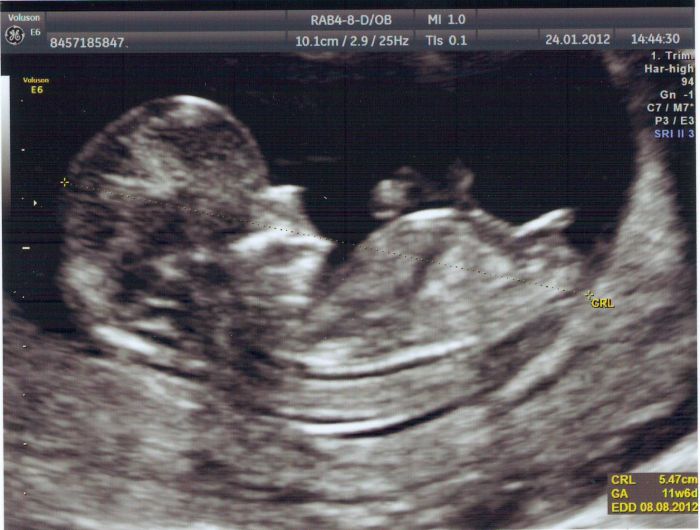

Přidávám fotku za včerejška, my by jsme chtěli kluka, pro holku nemáme zatím ani jméno

3.3. jdu k doktorce, třeba už se mezi nožkama něco klubat bude, nebo taky nebude